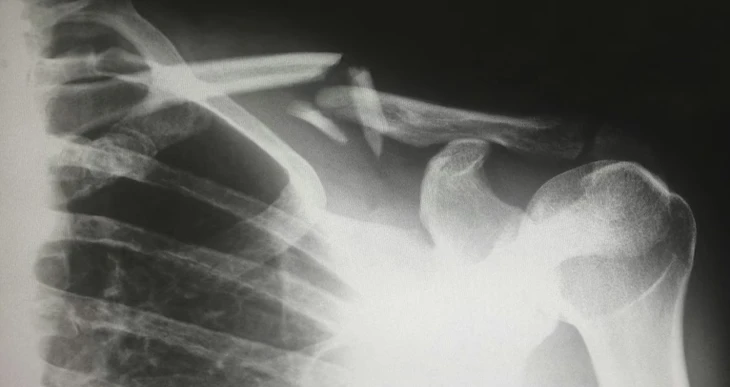

Các nhà khoa học Hàn Quốc vừa phát triển súng bắn keo in xương 3D giúp tái tạo xương ngay trong quá trình phẫu thuật, mở ra một kỷ nguyên mới trong phẫu thuật chỉnh hình.

Nếu các thử nghiệm lâm sàng trên người thành công, công nghệ mới của Hàn Quốc có thể thay thế nhiều kỹ thuật ghép xương truyền thống vốn tốn nhiều thời gian, chi phí và nguy cơ biến chứng hiện nay - Ảnh: Unsplash